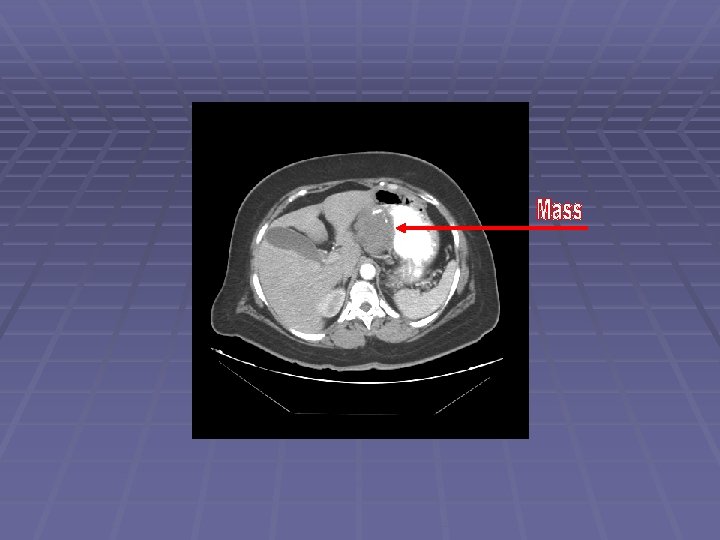

Liver Mass

FNA of Liver Mass

EUS Evaluation of Left Lobe of Liver